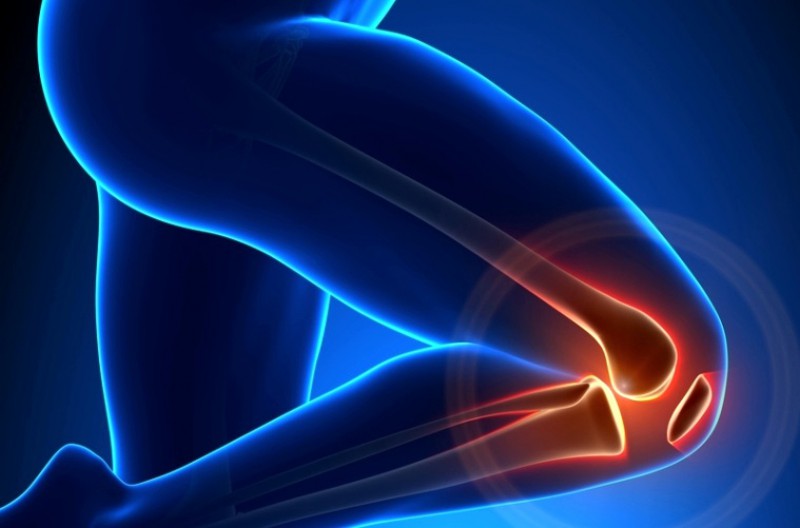

Meniscul este un cartilagiu care se gaseste in interiorul genunchiului intre femur si tibie, iar rolul acestuia este unul foarte important, acela de a amortiza si de a participa la stabilitatea articulara. Meniscul se rupe, de obicei atunci cand fortam genunchiul, dar exista si cazuri in care rupture poate fi degenerativa, ceea ce inseamna ca ruptura se produce din cauza tesutului extrem de uzat. Un set de radiografii, sau mai exact un RMN va poate spune exact daca suferiti de ruptura de menisci si apoi se recomanda in functie de gravitate, interventia chirurgicala, repaus, fizioterapie sau o orteza pentru genunchi.

Tratarea rupturii de menisc fara chirurgie! In functie de gravitate, dar si de fiecare pacient in parte, cat de bine raspunde acesta la tratamentul cu repaus, medicamente si fizioterapie, meniscul se poate vindeca in timp si fara interventii chirurgicale. Pentru o vindecare mai rapida, foarte multi medici aleg ortezele medicale deoarece sustin zona afectata, restrictionand indoirea acestuia, dar si exercitii recomandate de un kinetoterapeut. Orteza este rcomandata si dupa interventia chirurgicala in cazul in care este nevoie, deoarece protejeaza sutura pentru primele 4-6 saptamani, permitand zonei sa se vindece.

Ortezele va vor permite sa va intoarceti cat mai repede la activitatile dumneavoastra de zi cu zi mai repede decat va imaginati, intoarcerea la sport va poate fi permisa in 4-8 saptamani dupa interventia chirurgicala daca totul decurge bine, dar pentru acest lucru trebuie sa aveti o mobilitatate buna, tonus muscular si un control bun al genunchiului.